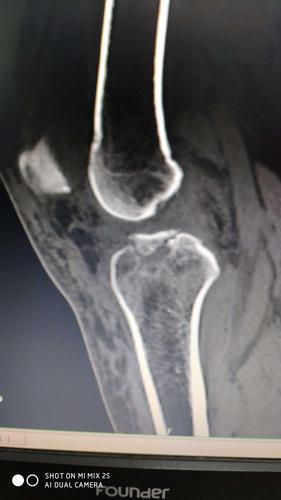

股骨内侧髁骨折,胫骨平台骨折,髁间嵴撕脱骨折.

髁间棘骨折

胫骨髁间骨折图片

胫骨髁间棘骨折图片

胫骨髁间骨折

胫骨髁间棘撕脱性骨折

胫骨髁间隆突骨折